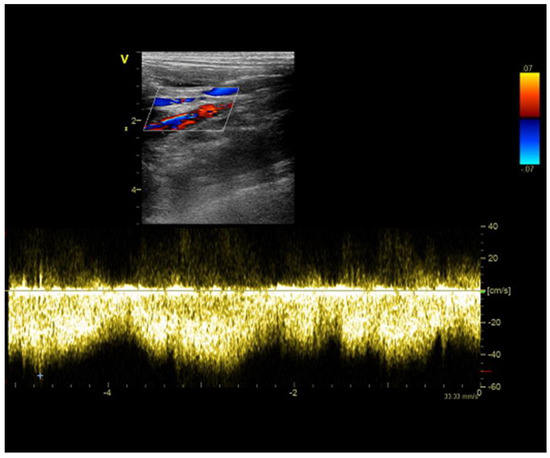

2.3. Case C (Dog)

2.4. Case D (Dog)

2.5. Case E (Cat)

6.5. Portal Vein Blood Flow

6.6. Portal Vein Tributaries